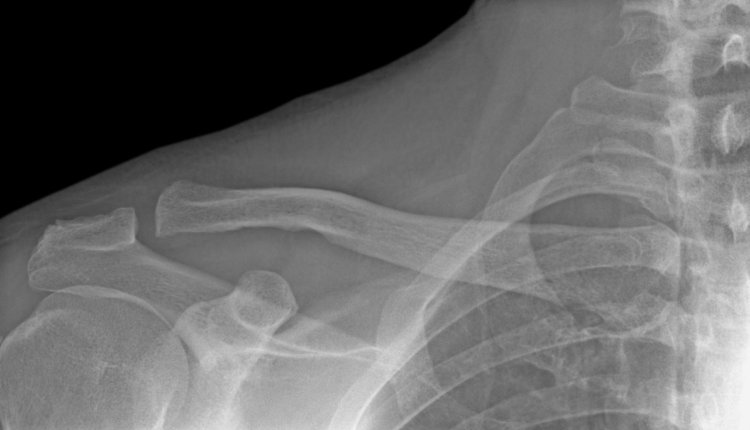

Klap tegen sleutelbeen

Mijn echtgenote, 68 jaar, ging laatst met een van onze kleinkinderen van een zwembadglijbaan, waarbij ze met haar sleutelbeen tegen de rand klapte. De huisarts zei dat het gekneusd was en het zou met rust weer goed komen. Maar de pijn wordt erger, ook als ze haar arm niet belast. De pijn loopt door naar haar vingertoppen en borst en ze heeft nu ook last van haar andere arm. Wat kan dit zijn?

Een klap tegen het sleutelbeen kan ook schade geven in de schouder en bij het borstbeen. Daar kunnen banden worden opgerekt, wat pijn kan doen maar wat ook abnormale beweeglijkheid kan geven in het gewricht. Daardoor gaat uw echtgenote waarschijnlijk de schouder ontzien. Hierdoor verkrampen nog meer spieren, wat nog meer pijn geeft. Uiteindelijk kunnen er zelfs zenuwen beklemd raken, wat de pijn in de vingertoppen verklaart. Als het steeds erger wordt, doet ze er verstandig aan een fysiotherapeut te bezoeken. Die maakt de schouder dan los.